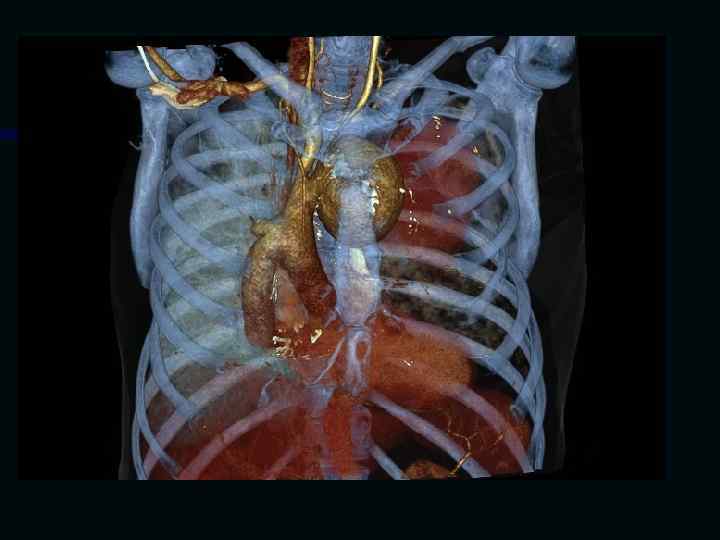

Исследование сосудов грудной клетки

Исследование сосудов брюшной полости